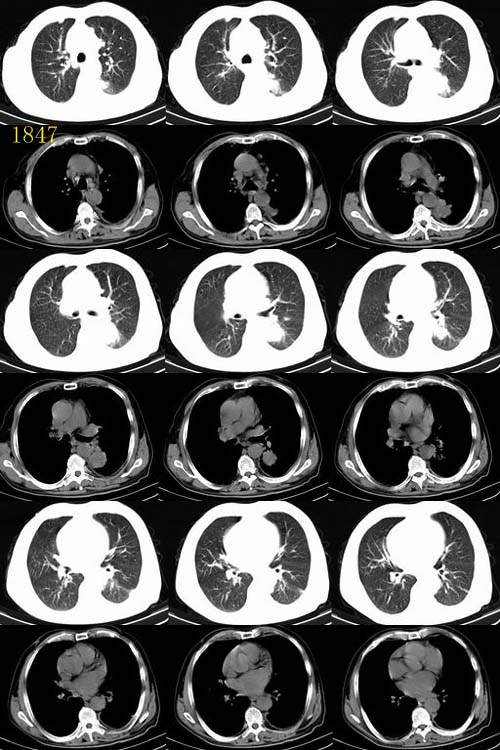

ct1847 九目段提供

m/71y,咳嗽咳痰,痰中带血,低热。

http://www.radida.com/radinet/read.php?tid=7356